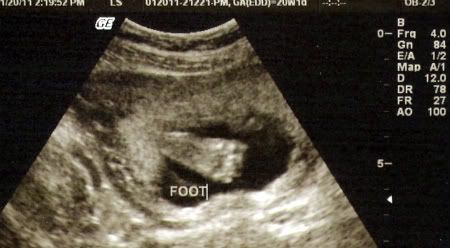

But baby girl T is measuring right on time (to the day!) and everything looked great so far. She weighs nearly a pound now, which is hard to believe! And she has definitely changed a LOT since we saw her a month ago! The u/s tech also pointed out her looooong legs, which was so cute to see. She definitely gets that from my side of the family! And here are two pictures I love. We couldn't get any great ones of her face because she was laying on my bladder and covering her face with her hands.

crossing her legs!